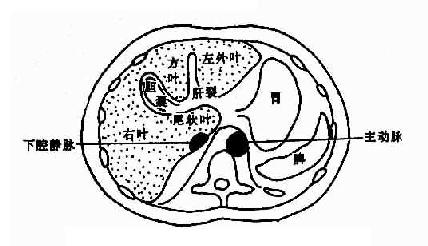

正常肝轮廓光滑,其形状及胸部结构依断面位置而不同。肝门区常有较多脂肪组织,呈不规则形或类似多角形低密度影。其中有肝动脉、门静脉和胆管进出。门静脉较大而居后,肝动脉位于其前内,胆管(主要是肝总管)位于其前外方。增强后门静脉较易识别,呈圆形高密度影,位于下腔静脉之前。CT上易于区分肝的各叶,即左呈、方叶、右叶和尾叶。左叶和方叶以圆韧带裂(又称纵裂)为界:方叶与右叶以右切迹和胆囊窝为界;横行的静脉韧带裂更明显。将左叶与尾叶分开;尾叶与右叶相连,突向内侧,位于下腔静脉的前方,易于识别。不同层面肝的解剖结构见图4-3-4。

图4-3-4 肝不同层面CT表现